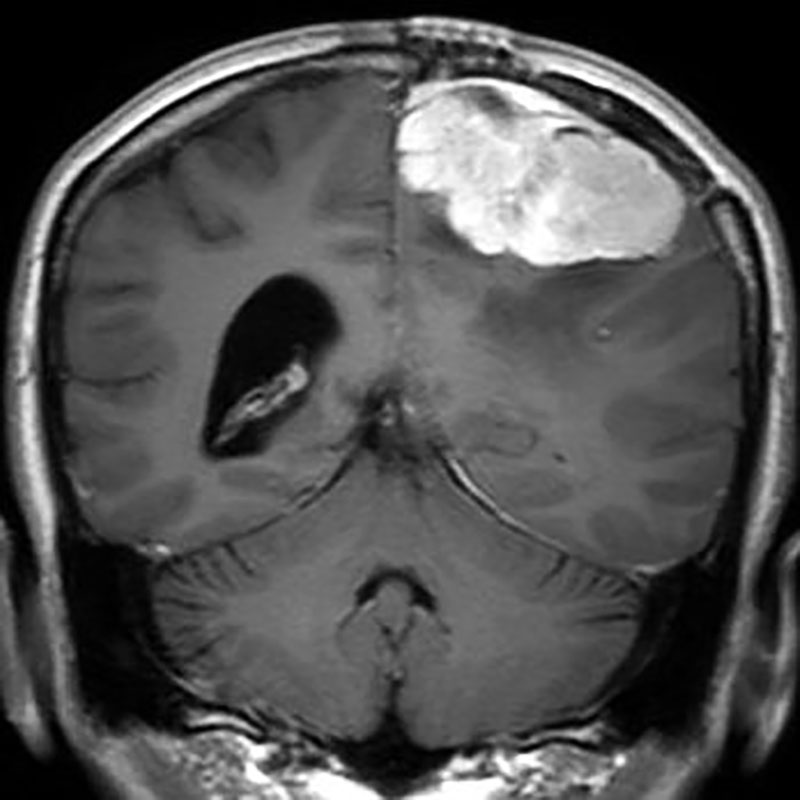

285

'22年4月

70代

膠芽腫

頭蓋内腫瘍摘出術

No.’22_42 手術前1

No.’22_42 手術前2

No.’22_42 摘出 前

No.’22_42  摘出 中

No.’22_42 摘出 後